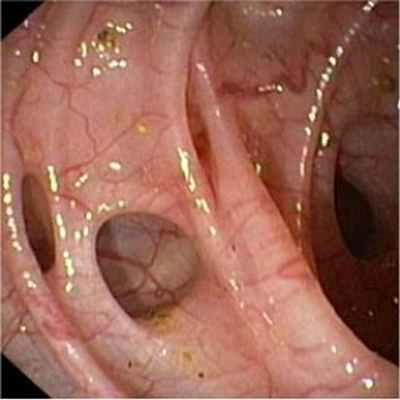

Клинические проявления дивертикулеза толстой кишки и его осложнений не могут служить основанием для установления точного диагноза заболевания. Диагностика и дифференциальная диагностика дивертикулеза толстой кишки основывается на анализе клинических проявлений заболевания и результатах обязательного рентгенологического и эндоскопического исследований толстой кишки.

- Колоноскопия позволяет выявить наличие множественных дивертикулов, признаков воспаления или кишечного кровотечения, а также может оказаться полезной для обнаружения таких сопутствующих поражений как полипы и рак.